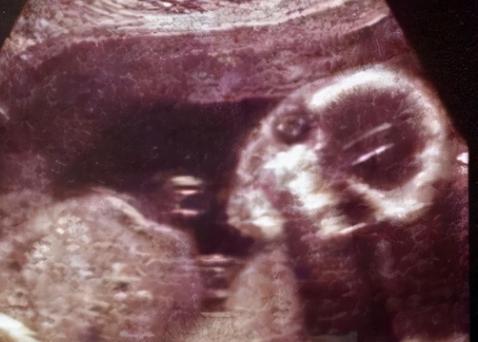

很快检查结果出来了,可等到刘安彬拿到拍好的片子一看时,却顿时愣住了,因为他发现,在老人的腹部竟然有一个四肢完全的胎儿!

“这个胎儿身体是躬起来的,四肢健全,是一个发育完全的胎儿!”刘安彬拿着片子,十分震惊地对罗炳文说道。

而刘安彬似乎是看出了罗炳文的不信任,所以就一手拿起拍好的片子,一手指着上面说道,“这里,老人的下腹处是胎儿是头骨。”

随后刘安彬不断的指着片子,一下一下的细说,慢慢的一个完整的胎儿形状就呈现在众人面前。

看着刘安彬医生手中的片子,再对照所说的话语,罗炳文自己也渐渐看出了胎儿的头部,脊椎,四肢和肋骨。

也就是说,刘安彬做出的判断是完全正确的,自己母亲的腹部里,真的有一个发育完全的胎儿!

“胎儿是和脊柱重叠在一起的,这说明他是在腹腔里,如果是在子宫内,他不应该和这个脊柱重叠起来。”医生这样说道。